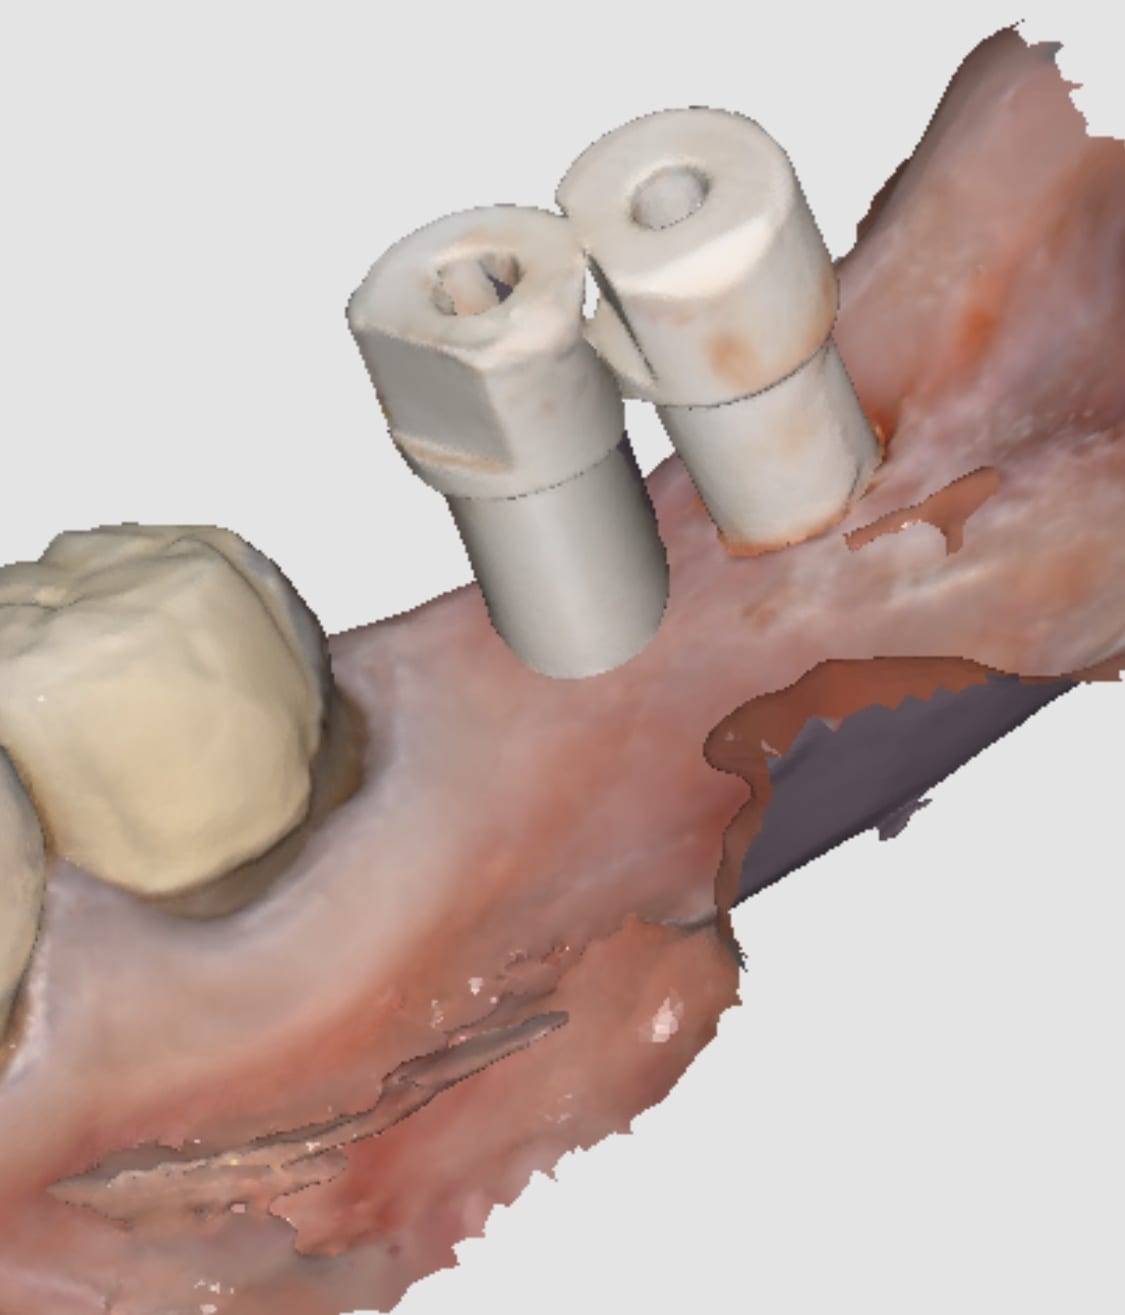

“Yes it can

I would however do separate abutments and crowns just in case you bind somewhere you can adjust crowns separate from abutments

You would have struggle with analog impressions

This is THE indication for digital dentistry over analog impressions!

I’m stealing this photo for my presentations 😉”